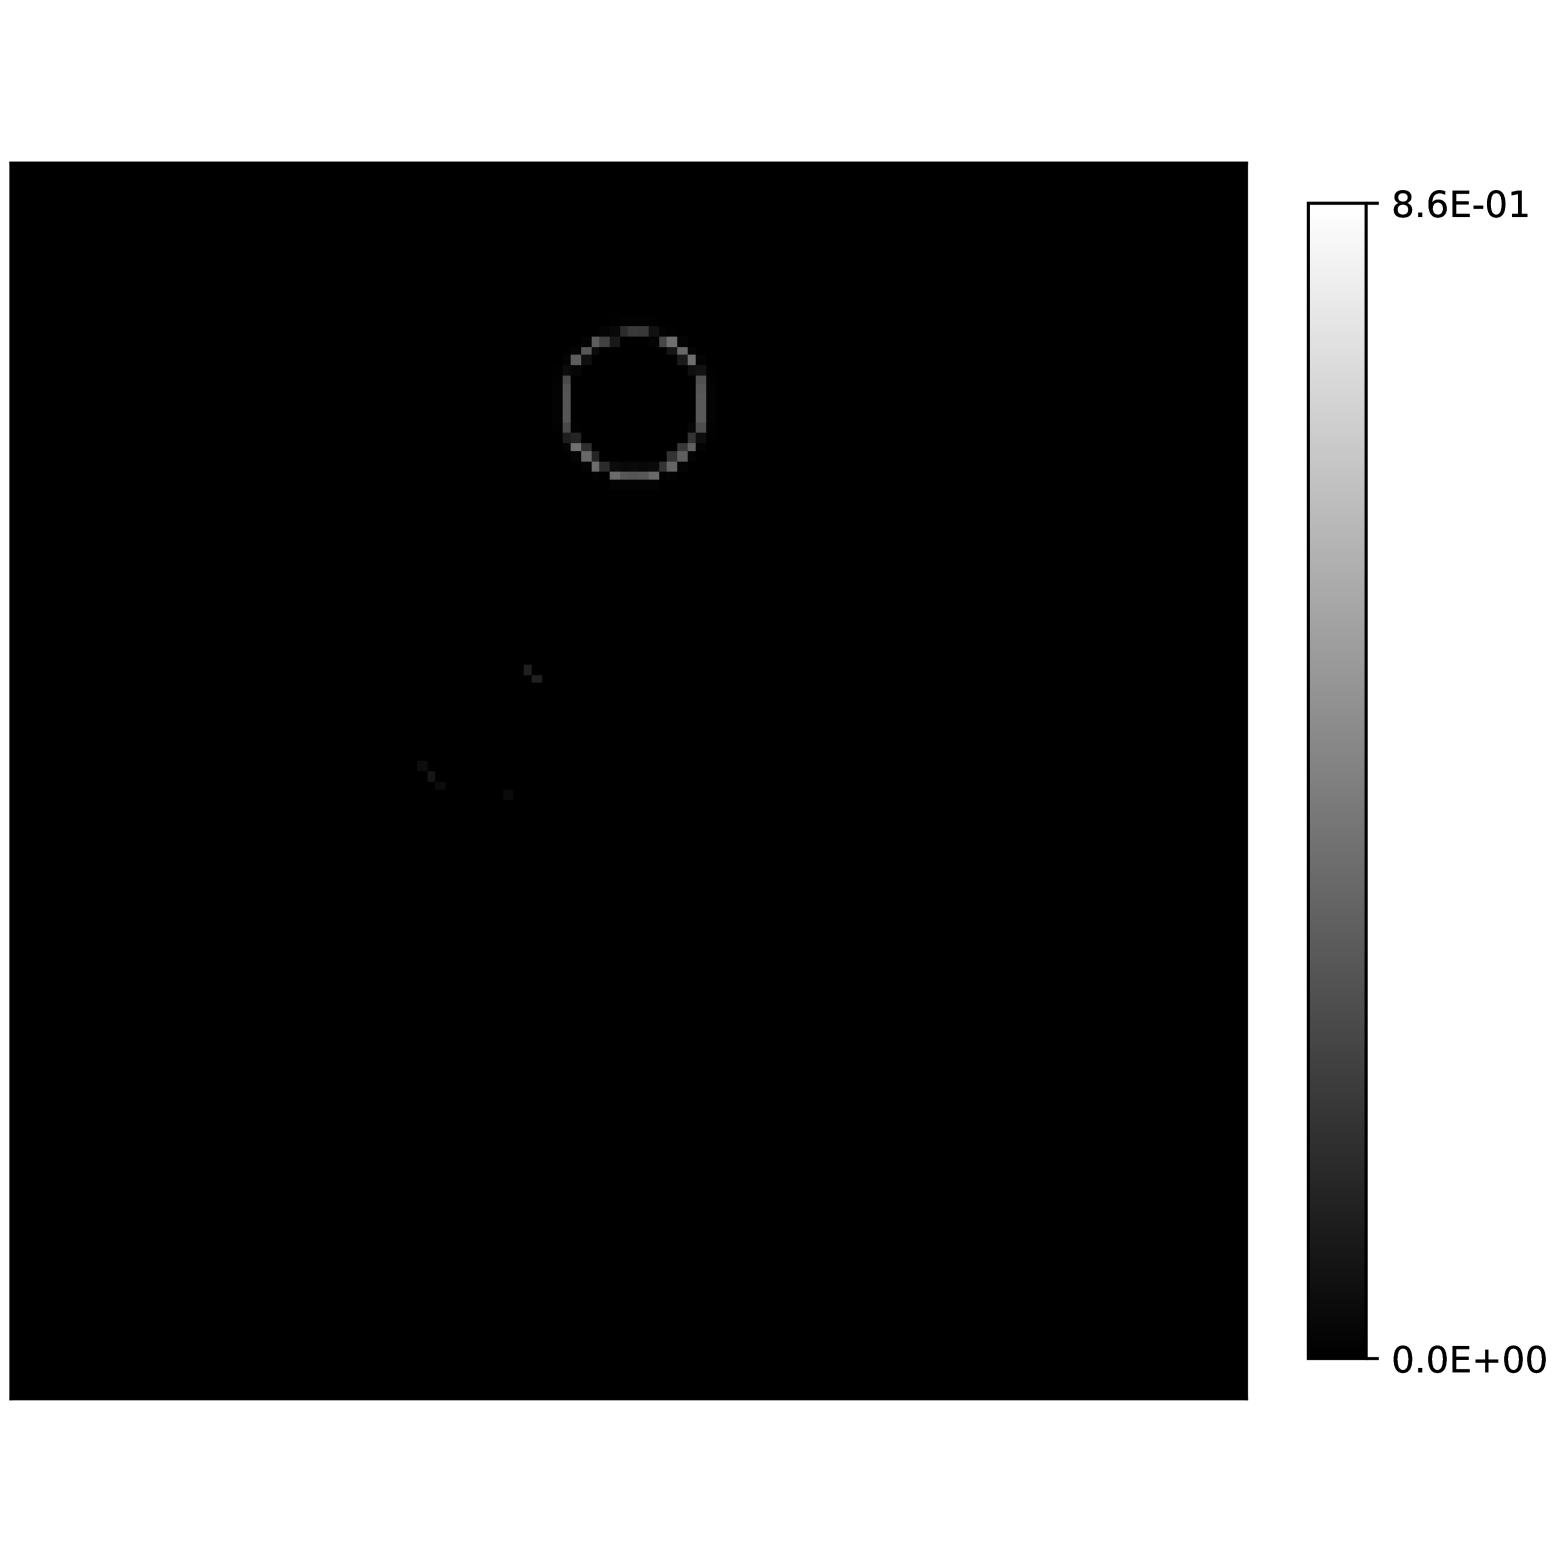

The fact that there is a neighborhood of around which the residual has positive curvature is critical to have local recovery conditions. We can compute this radius explicitly when the true parameters are known. We do this for a water, fat and silicone in silico phantom (see Section 5.3 below) and we evaluate the bounds that we provided for this radius in Theorem 3.1. Fig. 1(e) shows

for every voxel in the image. This quotient decreases by 50% in a range between Hz to Hz and reaches zero by to more than 60Hz. This shows that the curvature of the residual can vary significantly between voxels. Fig. 1(f) shows the radius at which the value attains 50% of its value, illustrating the spatial dependence on the signal at each voxel. Fig. 1(g) shows the estimates found by the bound in Theorem 3.1. As discussed earlier, it severely underestimates the radius, attaining a maximum value of Hz. In contrast, in Fig. 1(h) we show the estimate found using the improved bound in (31). As can be seen, although it still underestimates the radius, it provides a bound of Hz.